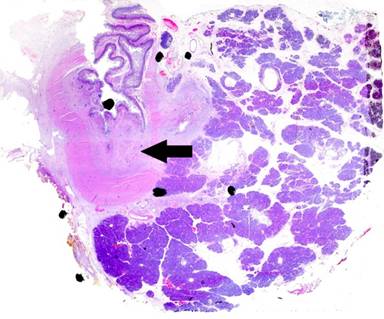

On histological analysis, an ill-defined lesion measuring 12 mm in maximum dimension was noted near the ampulla, extending to its anterior margin (Figure 1). The tumour measured 30 mm in maximum dimension within the duodenal submucosa, from where it ulcerated into the duodenal mucosa, surrounding blood vessels, the ampullary duct and the common bile duct (Figure 2). It infiltrated the duodenal muscularis propria and extended into the pancreatic parenchyma, reaching 16 mm from the superior mesenteric vein. Although there was extensive perineural invasion with infiltration of the duodenal mucosal and submucosal lymphatics, the pancreatic resection margin was not involved, and 0/13 peripancreatic and 0/10 greater curve lymph nodes were all free of tumour (T3N0M0). Microscopic appearances showed a poorly-differentiated signet-ring cell carcinoma, composed entirely of round cells containing intra-cytoplasmic mucin (Figure 3). Immunohistochemical staining was strongly positive for cytokeratin (CK) 7, CK20, CK8/18, CK19, CEA mono, CA 19-9, CA 125, MUC1 and MUC5AC. Tumour cells showed no expression for MUC2, MUC6, SMAD4, CDX2, ER and PgR. This immunohistochemical staining pattern is highly suggestive of signet-ring cell carcinoma of pancreatobiliary origin [3].

Figure 2. Histological section (H&E, x20) showing a diffuse tumour (arrow) located mainly within the duodenal mucosa, encircling the ampullary duct and extending into the pancreatic parenchyma. |